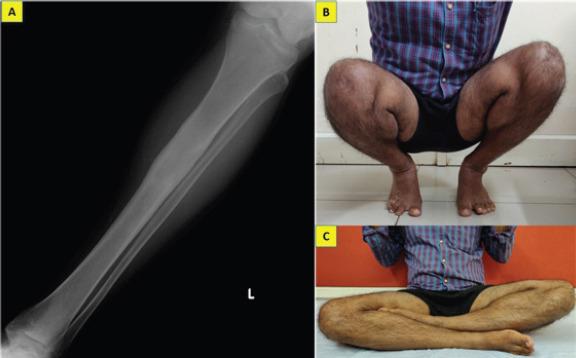

We report the case of a 31-year-old farmer who presented with long standing inconspicuous pain in his left leg which turned out to be a diaphyseal enchondroma even though it demonstrated aggressive radiological features mimicking a chondrosarcoma. Incisional biopsy was done from the scalloped areas to obtain the correct histological diagnosis. He underwent thorough curettage of the lesion and remains asymptomatic 2 years after the procedure. We attempt to discuss the differentials which the orthopedic surgeon should keep in mind for diaphyseal lesions mimicking enchondroma.

我们报告一例31岁农民的病例,他左腿长期存在不明显的疼痛,结果发现是骨干内生软骨瘤,尽管其放射学表现具有侵袭性,类似软骨肉瘤。从扇贝样区域进行了切开活检以获得正确的组织学诊断。他接受了病变的彻底刮除术,术后2年仍无症状。我们试图讨论骨科医生对于模仿内生软骨瘤的骨干病变应牢记的鉴别诊断。